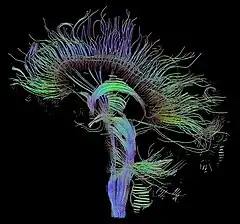

Diffusion-weighted magnetic resonance imaging (DWI or DW-MRI) is the use of specific MRI sequences as well as software that generates images from the resulting data that uses the diffusion of water molecules to generate contrast in MR images.[1][2][3] It allows the mapping of the diffusion process of molecules, mainly water, in biological tissues, in vivo and non-invasively. Molecular diffusion in tissues is not random, but reflects interactions with many obstacles, such as macromolecules, fibers, and membranes. Water molecule diffusion patterns can therefore reveal microscopic details about tissue architecture, either normal or in a diseased state. A special kind of DWI, diffusion tensor imaging (DTI), has been used extensively to map white matter tractography in the brain.

The principal application is in the imaging of white matter where the location, orientation, and anisotropy of the tracts can be measured. The architecture of the axons in parallel bundles, and their myelin sheaths, facilitate the diffusion of the water molecules preferentially along their main direction. Such preferentially oriented diffusion is called anisotropic diffusion.

The imaging of this property is an extension of diffusion MRI. If a series of diffusion gradients (i.e. magnetic field variations in the MRI magnet) are applied that can determine at least 3 directional vectors (use of 6 different gradients is the minimum and additional gradients improve the accuracy for "off-diagonal" information), it is possible to calculate, for each voxel, a tensor (i.e. a symmetric positive definite 3×3 matrix) that describes the 3-dimensional shape of diffusion. The fiber direction is indicated by the tensor's main eigenvector. This vector can be color-coded, yielding a cartography of the tracts' position and direction (red for left-right, blue for superior-inferior, and green for anterior-posterior).[45] The brightness is weighted by the fractional anisotropy which is a scalar measure of the degree of anisotropy in a given voxel. Mean diffusivity (MD) or trace is a scalar measure of the total diffusion within a voxel. These measures are commonly used clinically to localize white matter lesions that do not show up on other forms of clinical MRI.[46]